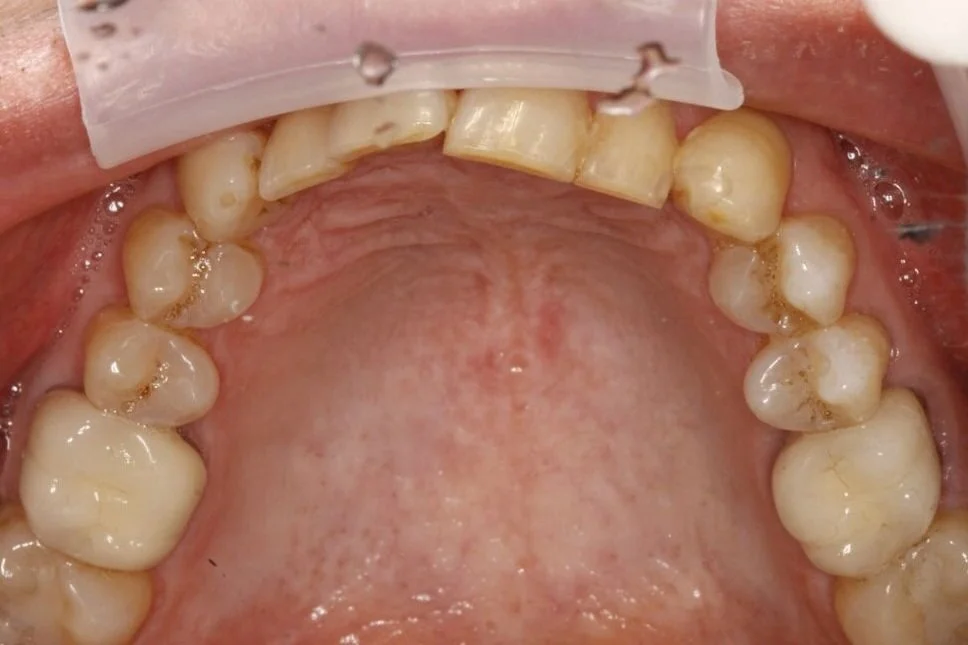

Gallery Dental Designs Roseville, CA Teeth Whitening Roseville Professional dental services in roseville, ca and greater sacramento area. Teeth whitening, root canals, cosmetic dentistry, implants and more. Whitening in roseville, lincoln, and neighboring areas. Teeth whitening is a cosmetic dental procedure designed to lighten the color of your teeth and remove stains and discoloration. If you want to enhance your smile's appearance, professional teeth whitening may be the. Teeth Whitening Roseville.